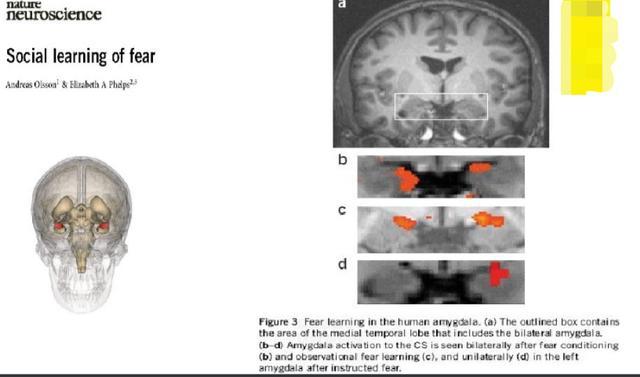

如下这张图,是人类大脑的恐惧中心部位,杏仁核所在的位置,见a图的方框位置。

b,c,d是不同情况下对应大脑的恐惧中心活化的情况。

b图是只要铃声一响,大脑的恐惧中心立即活化,也就是此时,电还没有出来,但是大脑知道电要来了,于是立即恐惧起来。

c图则是看着被电的人的大脑图,恐惧中心也是活化的,也就是看着别人被惩罚,看的人也一样恐惧。

d图则是电左边的手,大脑右边恐惧中心活化。

- b图说明期待被处罚与处罚时的恐惧是一样的。

- c图则说明杀鸡儆猴的道理所在。